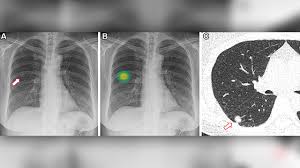

- 흉부 X‑선 또는 흉부 CT로 발견

- 결절 크기·형태·경계·석회화 여부 등 특징 분석

- 의심되는 경우 PET-CT 스캔 또는 조직 생검 시행